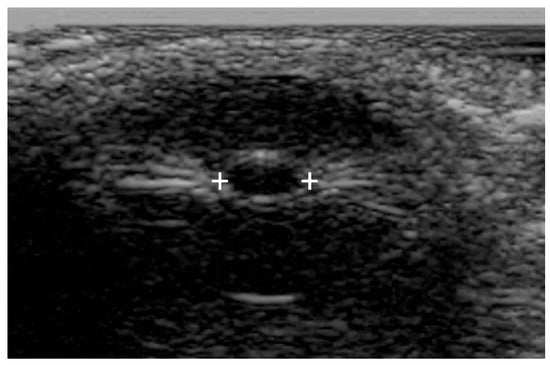

Commercially available PAIPs lack the capability for bilateral observation, rendering the assessment of relative afferent defects impossible. Furthermore, the use of currently available commercial PAIPs with fixed light intensity and duration may affect the sensitivity of the examination. Finally, agitated or confused patients as well as patients with scleral or periorbital edema, intraocular lens replacement, or prior ocular surgical procedures can be difficult to evaluate [77,78]. Ultrasound pupillometry can be applied in some cases [79] of facial or orbital trauma, but there are currently no automated portable devices offering standardized ultrasound measurements (Figure 4).

Figure 4.

Bedside or portable ultrasound can be used to assess the pupillary reactivity when one or both eyes cannot be opened. Pupillary size is indicated by the plus signs.